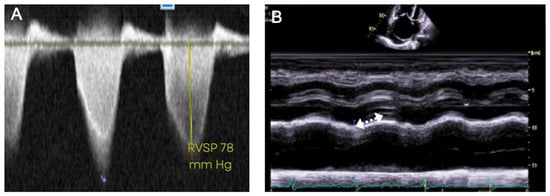

5.3. Transthoracic Echocardiography

| TTE [17] | 83% | 72% | Useful initial noninvasive modality for screening and measurement of pulmonary pressures. | Dependence on the quality of imaging, difficulty in image acquisition with increased RV volumes, steady heart rate, and experience of the laboratory staff. |